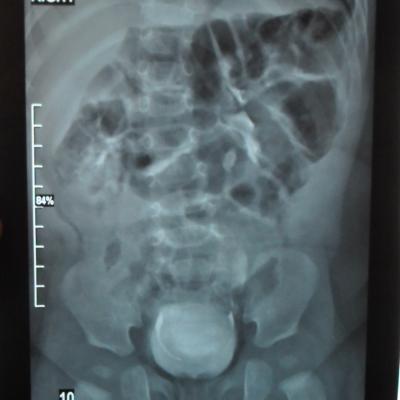

Моему ребенку 1 год 1 месяц. Во время беременности у плода было обнаружено увеличение лоханки слева - 9мм. Далее по результатам УЗИ после рождения максимальное увеличение достигало 17 мм. В 5 месяцев проходили урологическое обследование, результаты цистографии: мочевой пузырь округлой формы. Контуры ровные. ПМР нет. ЭЭД-1,2МЗВ; урографии: рентгеноконтрастных теней конкремента нет, почки в типичном месте, размеры сохранены, структура ЧЛК справа не изменена, слева пиелоэктазия, подвижность допустима, функция сохранена, ЭЭД – 0,4 МЗВ. По последнему УЗИ (1 год) увеличение лоханки слева - 28 мм. Мочеточники и сама почка в норме. Результаты анализов мочи за этот год хорошие (сдавали ежемесячно). В чем могут быть причины данного явления и чем это грозит малышу?

Ответ врача

В данном случае - сужение лоханочно-мочеточникового сегмента и\или добавочный сосуд(слева). Но выделительная функция почки сохранена. В данный момент целесообразно наблюдение, но в дальнейшем - не исключено хирургическое вмешательство.